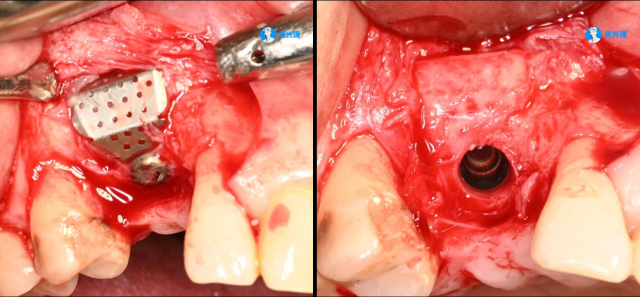

病例展示二

微信图片_2025-07-15_091825_179.jpg

微信图片_2025-07-15_092131_722.jpg